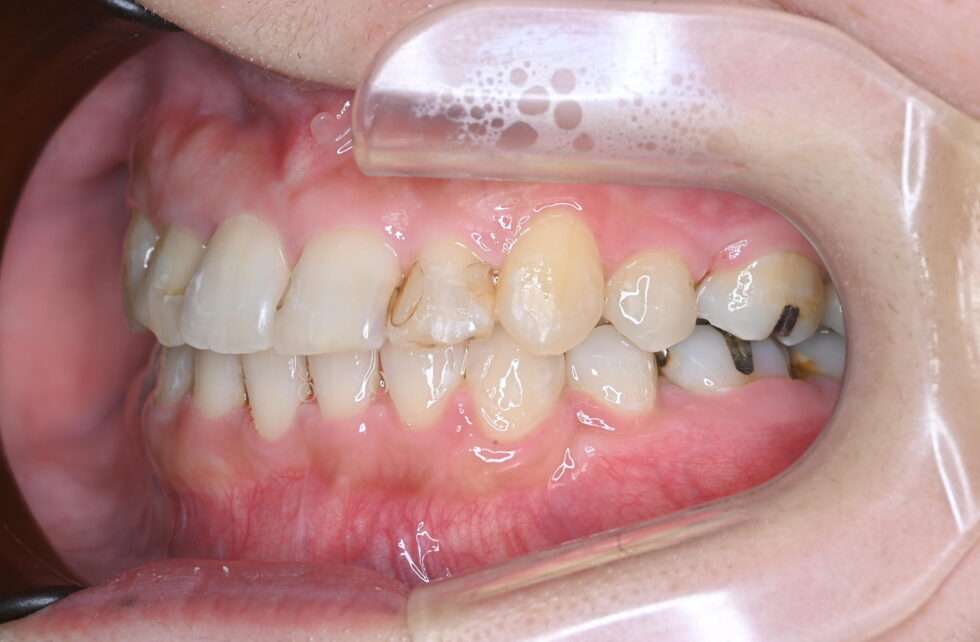

初診時年齢32歳の女性 前歯部の叢生と反対咬合を主訴にご来院いただいた

上顎は右側側切歯が口蓋側転位となり、その分上顎の正中線は右側へ4㎜程度偏位していた。また、右側第二小臼歯は残根状態で歯冠が無かった。さらに、左側中切歯、側切歯は反対咬合となっていた。上顎右側に矯正用アンカープレートを植立し、上顎は左右側第二小臼歯、下顎は左右側第一小臼歯を抜歯していただきマルチブラケット装置を使用して動的治療を行った。上顎右側側切歯が完全に口蓋側転位になっているにもかかわらず、残根となっていた第二小臼歯を抜歯する必要があったため、上顎右側第一小臼歯と犬歯の遠心への移動に時間がかかり動的治療期間は3年5ヵ月間を要した。(調整来院30回)しかし、可能な限り健全な歯を残すことができた。また、虫歯のリスクが高い方であったが歯列が整ったことでセルフケアがしやすくなった。